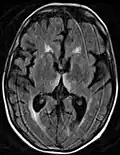

Frequently, secondary to thiamine deficiency and subsequent cytotoxic edema in Wernicke encephalopathy, patients will have marked degeneration of the mammillary bodies. Thiamine (vitamin B1) is an essential coenzyme in carbohydrate metabolism and is also a regulator of osmotic gradient. Its deficiency may cause swelling of the intracellular space and local disruption of the blood-brain barrier. Brain tissue is very sensitive to changes in electrolytes and pressure and edema can be cytotoxic. In Wernicke this occurs specifically in the mammillary bodies, medial thalami, tectal plate, and periaqueductal areas. People with the condition may also exhibit a dislike for sunlight and so may wish to stay indoors with the lights off. The mechanism of this degeneration is unknown, but it supports the current neurological theory that the mammillary bodies play a role in various "memory circuits" within the brain. An example of a memory circuit is the Papez circuit.